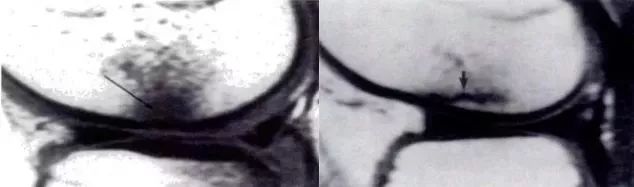

MRI 是诊断微小骨折和不完全性骨折的「金标准」,国外有学者比较了 CT 和 MRI 在评估髋部隐匿性骨折方面的优势,认为 MRI 优于 CT(图 1),但 MRI 的准确诊断较难,需要经验丰富的影像科医生仔细观察。

图 1 同一患者同一部位的 CT(a)和 MRI 图像(b,T1 相;c,STIR 相)。可见 CT 未发现骨折线,而 MRI 可明显看到骨折线。(图片摘自 Haubro M, et al. Injury,2015,46(8))